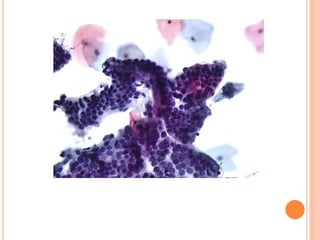

O hormônio que atua na maturação é o estrogênio. As células encontradas no Papanicolaou que sofrem a ação do estrogênio são as células escamosas. Estas células podem ser observadas no Papanicolaou principalmente na fase proliferativa do ciclo menstrual.